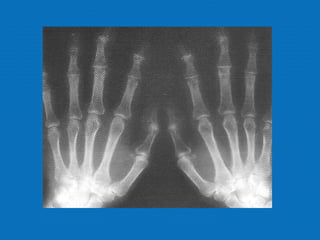

RADIOLOGIA

No início da doença não se observam anormalidades. Com seu

desenvolvimento, observam-se:

• Diminuição do espaço intra-articular

• Esclerose subcondral (eburnação)

• Osteófitos;

• Erosão e anquilose óssea (pseudocistos ósseos).

RADIOLOGIA No início dadoença não se observam anormalidades. Com seu desenvolvimento, observam-se: • Diminuição do espaço intra-articular • Esclerose subcondral (eburnação) • Osteófitos; • Erosão e anquilose óssea (pseudocistos ósseos).